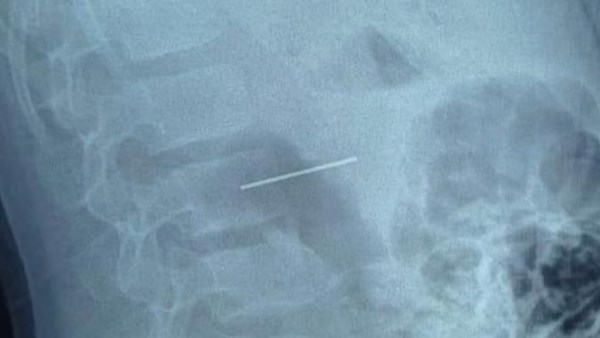

نجح قسم جراحة الأطفال بمستشفى الأطفال التخصصي ببنها في خروج مسمار دباسة كراسي اخترق جدار بطن طفل واستقر داخل التجويف البطني، بعد تدخّل جراحي متقدّم جمع بين المنظار الجراحي وجهاز السي أرم لتحديد الموقع بدقة متناهية.

قاد العملية فريق متميز: د. محمد متولي رئيس قسم جراحة الأطفال، وبمشاركة د. وليد محمد استشاري جراحة الأطفال ود. محمود ممدوح نائب قسم جراحة الأطفال. تم توظيف المنظار الجراحي لتقليل آثار الجراحة والشفاء السريع، فيما لعب جهاز السي أرم دور الخريطة الحية لتحديد موقع المسمار بدقة مدهشة، ما حول العملية إلى مزيج من مهارة الجراح وذكاء الأجهزة.

في غرفة العمليات ساد توتر محموم، ثم تصاعدت الدقات مع لحظة استخراج المسمار الحاد من داخل بطن الطفل. خرج المعدن الغريب تاركًا خلفه ارتياحًا فوريًا في ملامح الفريق وابتسامة تبدأ في العودة لوجوه الأهالي.